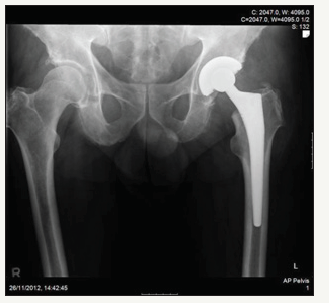

Case 6

A 58 year old male underwent left total hip arthroplasty for osteoarthritis. Implants used were a 54mm Pinnacle Duofix HA 100 series acetabular cup with a neutral Marathon polyethylene liner (28mm IDx54mm OD) implanted with a 28mm+1.5 Biolex Delta ceramic femoral head (12/14 taper) and uncemented No 12 lateral offset Corrail femoral component. Post-op course was uneventful with X-Rays showing 42° of cup inclination (Figure 24 & 25).

figure 24: Post-op left total hip arthroplasty.

figure 25: Post-op left total hip arthroplasty (lateral radiograph).

Four months later he was reviewed and reported four or five episodes of subluxation of the hip (whilst in the shower and when bending forwards to pick up socks). A month later he had a more severe episode in which the pain did not resolve and X-Rays showed an eccentrically positioned femoral head. He underwent revision where three of the six anti-rotation lugs were broken (although in this case the 3 were not adjacent lugs). The head was exchanged and a lipped polyethylene liner was placed. At 9 months post-op he continues to do well (Figure 26-29).

figure 26: Post-revision left hip arthroplasty.

figure 27: Post-revision left hip arthroplasty (lateral radiograph).